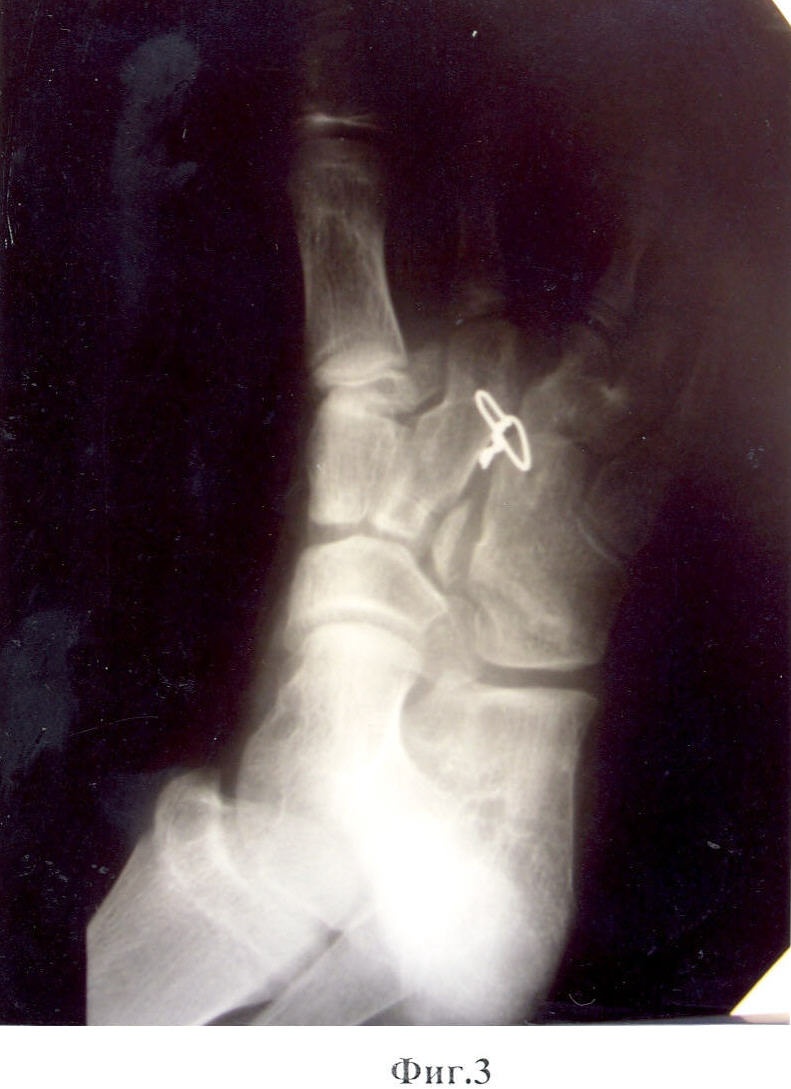

Предложенный способ иллюстрируют приведенные рентгенограммы и фотографии, где на фиг.1, 2 показан вид стопы до операции; на фиг.3, 4 – вид после операции; на фиг.5, 6 – снимок и фотография стопы через два месяца после операции.

Больной М-в, 12 лет. История болезни №6618. 11.12.2006 г. Поступил в отделение кисти «НИЦТ ВТО» с диагнозом: Сложное врожденное расщепление с элементами полидактилии, синостозом IV-V плюсневых костей и сверхкомплектом лучей обеих стоп (фиг.1, фиг.2).

21.12.2006 г. – больному была проведена операция по разработанной методике на правой стопе. Наркоз. Из разрезов по тыльной и подошвенной сторонам иссечены края расщелины стопы. С тыльного доступа удален III луч. Основание луча, прилегающее к II клиновидной кости, оставлено в виде костного фрагмента. Острым долотом с медиальной стороны кубовидной кости, ближе к основанию, поперечно длиннику стопы выбит костный клин, угол которого соответствует углу отклонения наружной половины расщепленной стопы от ее средней линии. Костный клин выбран так, что его вершина не доходит до наружного края кубовидной кости на 2-3 мм. Резецирован костный выступ по наружной стороне дистальной части II плюсневой кости. Через диафиз II плюсневой кости и дистальный отдел кубовидной кости поперечно с тыла на подошвенную сторону просверлены каналы. Через сформированные каналы проведена металлическая проволока так, чтобы концы ее вышли на тыл стопы. Обе половины расщепленной стопы с усилием смещены навстречу друг другу так, чтобы смежные стороны половин полностью сомкнулись. Концы проволоки с натяжением стянуты, скручены в узел и погружены в межкостную щель. Кожные швы до дренажей. Спиртовая повязка. Подошвенная гипсовая лонгета. Через две недели заживление раны первичным натяжением (фиг.3, фиг.4). Кожные швы сняты. Через 2 мес гипс снят. На контрольной рентгенограмме виден костный синостоз между фрагментом основания плюсневой кости и телом кубовидной кости (фиг.5, фиг.6). Больной начал нагружать правую стопу.